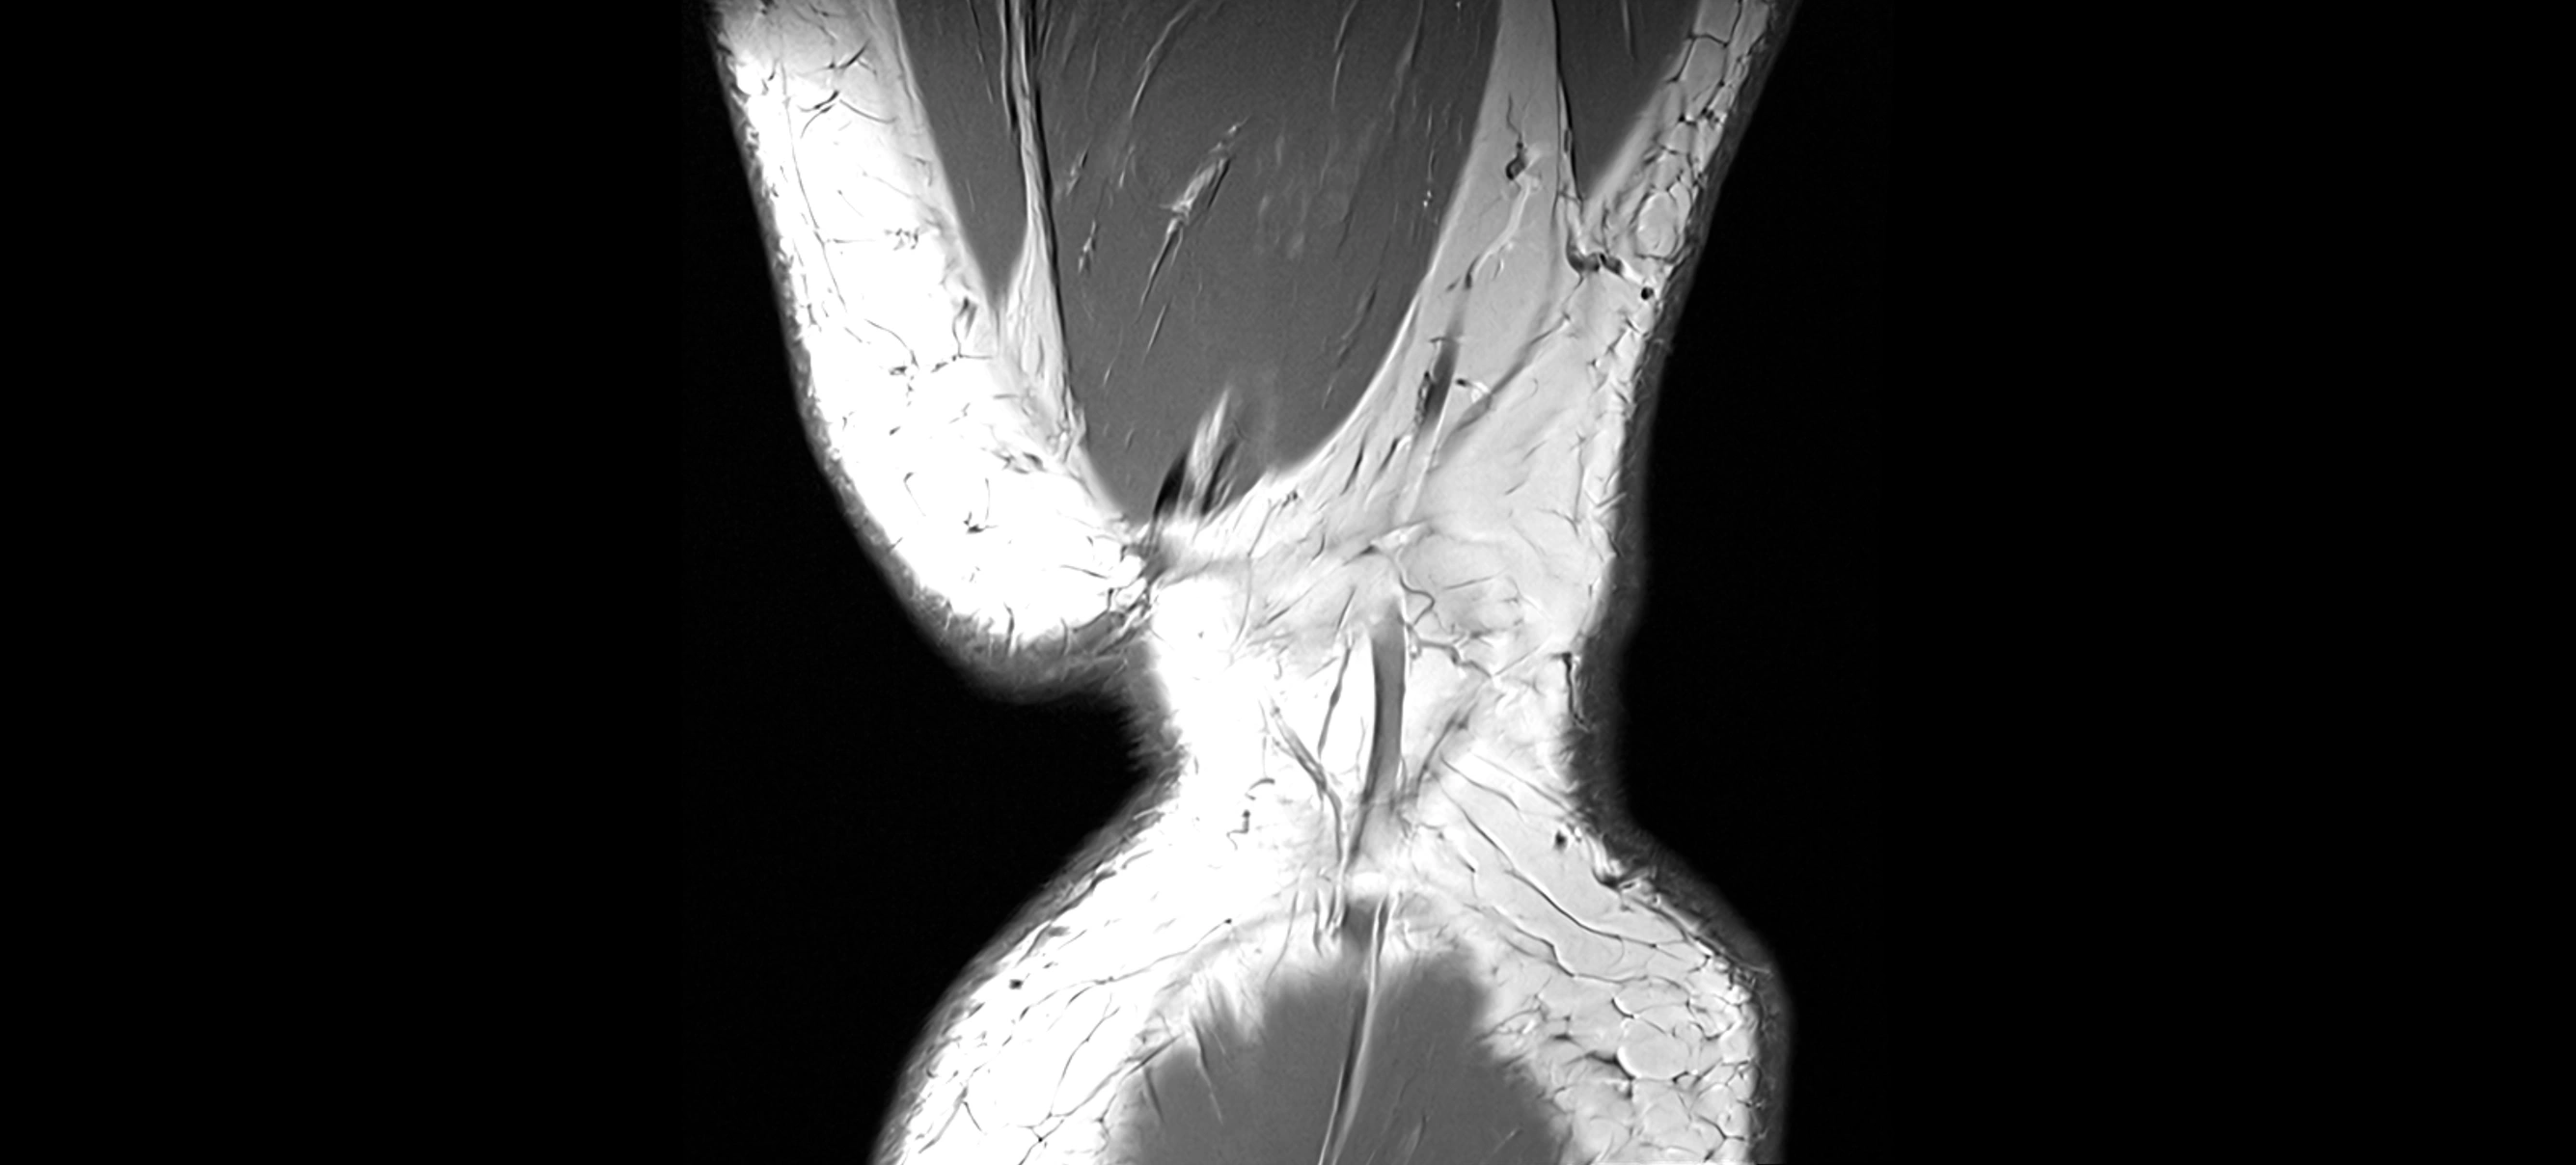

MRI images

image

CT image